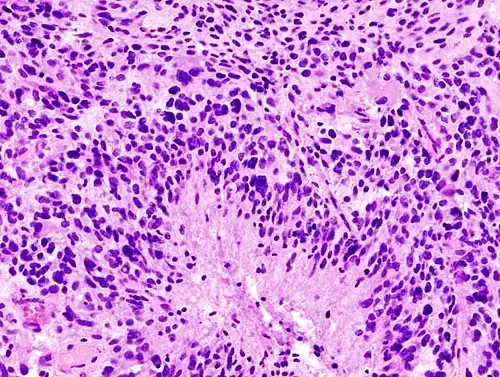

When viewed with MRI, glioblastomas often appear as ring-enhancing lesions. The appearance is not specific, however, as other lesions such as abscess, metastasis, tumefactive multiple sclerosis, and other entities may have a similar appearance.[61] Definitive diagnosis of a suspected GBM on CT or MRI requires a stereotactic biopsy or a craniotomy with tumor resection and pathologic confirmation. Because the tumor grade is based upon the most malignant portion of the tumor, biopsy or subtotal tumor resection can result in undergrading of the lesion. Imaging of tumor blood flow using perfusion MRI and measuring tumor metabolite concentration with MR spectroscopy may add diagnostic value to standard MRI in select cases by showing increased relative cerebral blood volume and increased choline peak, respectively, but pathology remains the gold standard for diagnosis and molecular characterization.

Distinguishing glioblastoma from high-grade astrocytoma is important. These tumors occur spontaneously (de novo) and have not progressed from a lower-grade glioma, as in high-grade astrocytomas.[6] Glioblastomas have a worse prognosis and different tumor biology, and may have a different response to therapy, which makes this a critical evaluation to determine patient prognosis and therapy.[45][62] Astrocytomas carry a mutation in IDH1 or IDH2, whereas this mutation is not present in glioblastoma. Thus, IDH1 and IDH2 mutations are a useful tool to distinguish glioblastomas from astrocytomas, since histopathologically they are similar and the distinction without molecular biomarkers is unreliable.[46] IDH-wildtype glioblastomas usually have lower OLIG2 expression compared with IDH-mutant lower grade astrocytomas.[63] In patients aged over 55 years with a histologically typical glioblastoma, without a pre-existing lower grade glioma, with a non-midline tumor location and with retained nuclear ATRX expression, immunohistochemical negativity for IDH1 R132H suffices for the classification as IDH-wild-type glioblastoma.[60] In all other instances of diffuse gliomas, a lack of IDH1 R132H immunopositivity should be followed by IDH1 and IDH2 DNA sequencing to detect or exclude the presence of non-canonical mutations.[60] IDH-wild-type diffuse astrocytic gliomas without microvascular proliferation or necrosis should be tested for EGFR amplification, TERT promoter mutation and a +7/–10 cytogenetic signature as molecular characteristics of IDH-wild-type glioblastomas.[60]

-

Histopathology of glioblastoma, showing high grade astrocytoma features of marked nuclear pleomorphism, multiple mitoses (one at white arrow) and multinucleated cells (one at black arrow), with cells having a patternless arrangement in a pink fibrillary background on H&E stain. -

Lower magnification histopathology, showing necrosis surrounded by pseudopalisades of tumor cells, conferring a diagnosis of glioblastoma rather than anaplastic astrocytoma